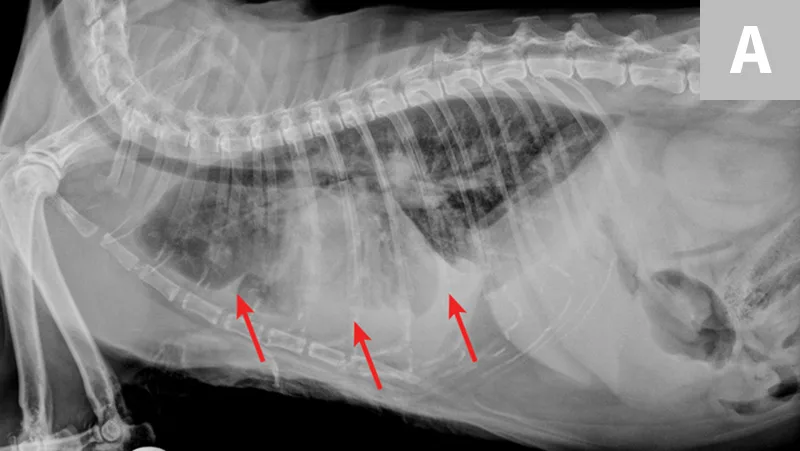

FIGURE 5A

Radiograph of aelurostrongylus abstrusus infection (lungworm). Note the diffuse bronchial pattern (orange arrows), patchy poorly defined soft-tissue nodules (red arrows), and right middle lung lobe alveolar disease (yellow arrow). This pattern could be confused with feline asthma in this case; however, the right middle lung does not appear atelectatic but instead infiltrated. Fine-needle aspiration of the right middle lung lobe confirmed larvae.